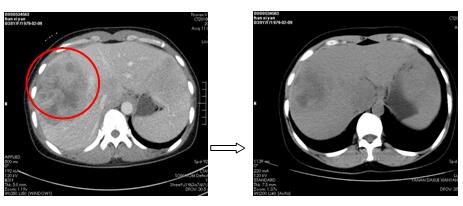

针对每一例化疗患者,参照最新NCCN指南(为肿瘤诊疗的国际权威指南),为患者制定规范、有效的个体化化疗方案。2周期化疗后评价疗效:其中1例肺癌肉瘤术后的胰腺占位的患者,2次化疗后胰腺占位基本消失,另有1例非小细胞肺癌伴肺、心包、肝多发转移患者,2次化疗后肺部、肝内病灶显著缩小,其余化疗患者还未到疗效评价时机(指南推荐每2周期评价化疗疗效)。

图1. 2周期化疗后胰腺区占位基本消失